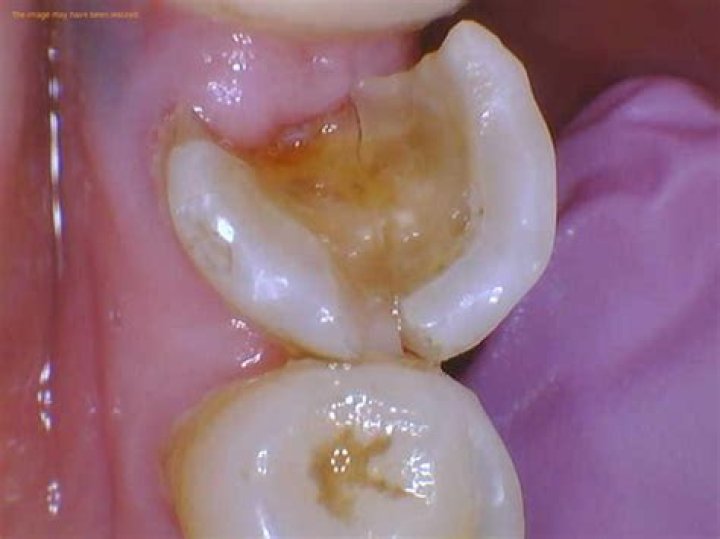

What does a rotten tooth look like?

If the process of tooth decay is allowed to continue, enamel will break down further. You may notice that a white spot on a tooth darkens to a brownish color. As enamel is weakened, small holes in your teeth called cavities, or dental caries, can form. Cavities will need to be filled by your dentist.

The possible causes of a chipped or cracked tooth include: Cavities: Cavities which can weaken the teeth and predispose you to a chipped tooth. Bad Bite: Biting down on something hard, such as an ice cube, a piece of hard candy, or a bone.

Why is my tooth turning black?

The tooth may also appear black when damage occurs from the inside. The most common causes of black teeth in these cases are decay or cavities. For example, a tooth with a pulp infection or a dead tooth may turn black. The damage starts on the inside and works its way to the surface.